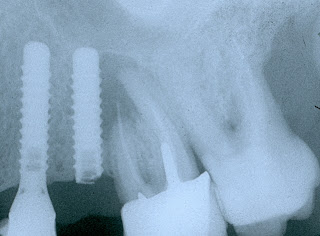

Radiografía dental mostrando perdida de hueso por peri implantitis |